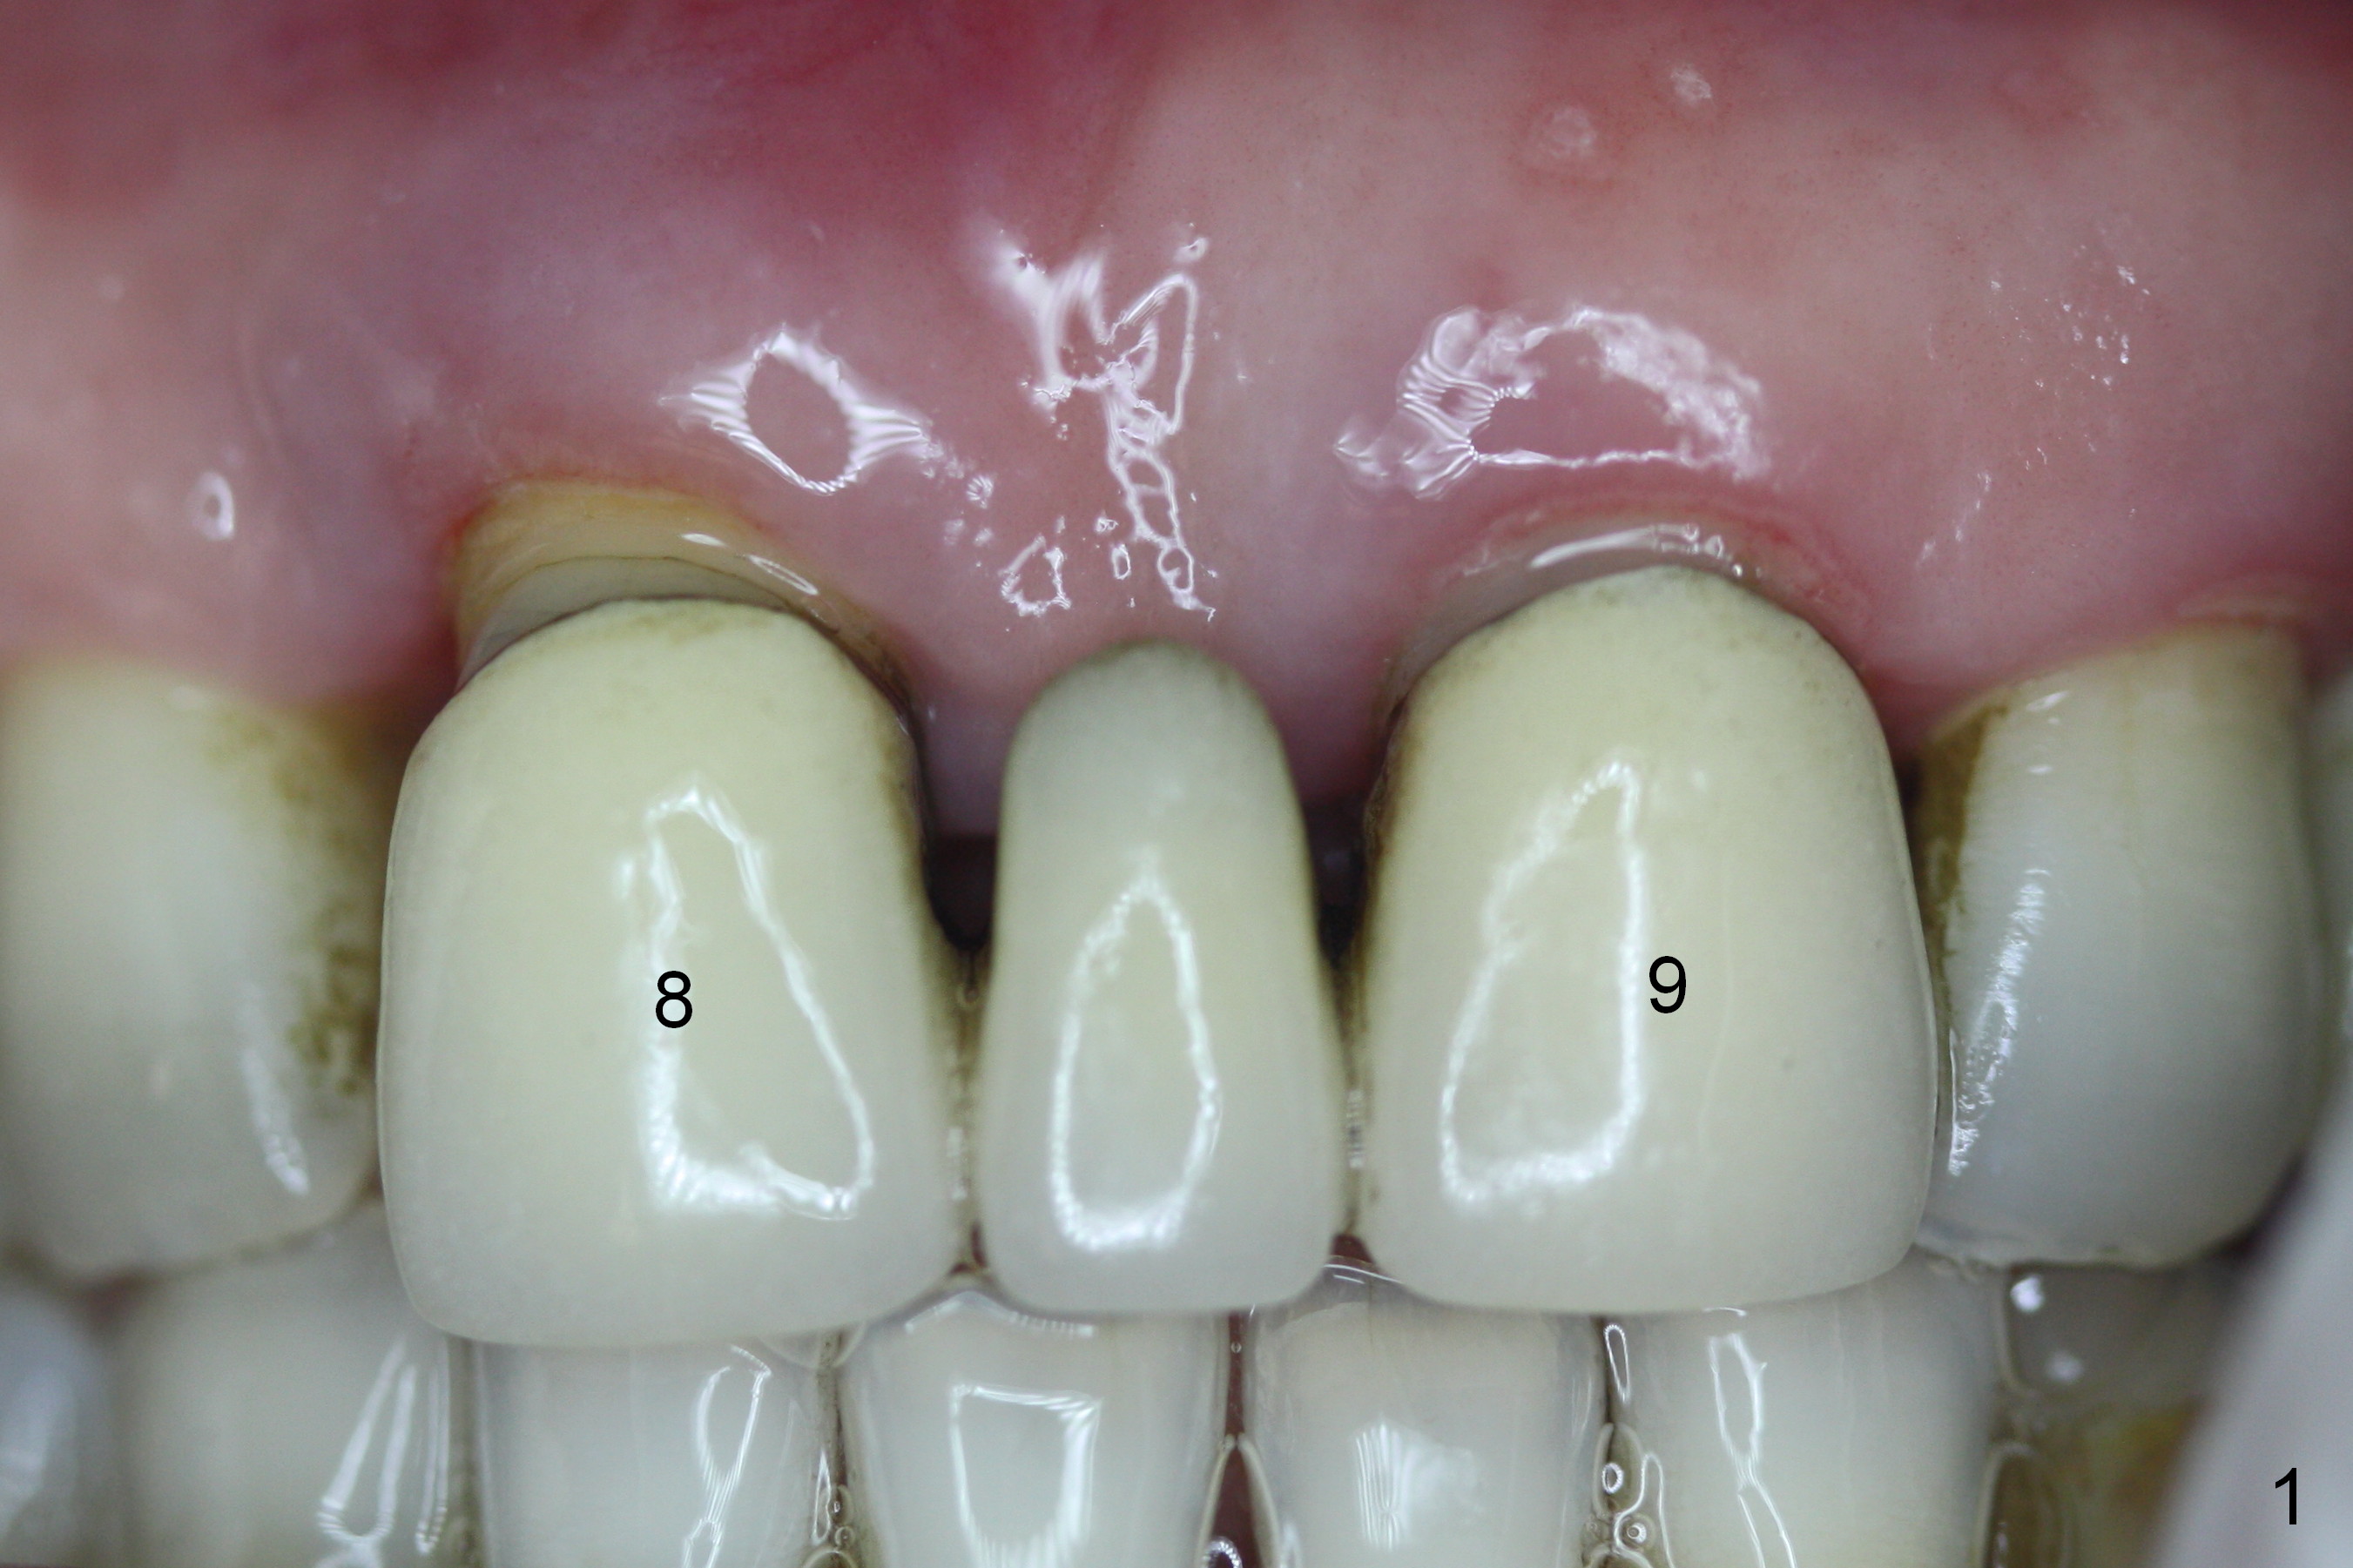

The 74-year-old patient is excited about having 3 implants placed without discomfort (1,2). He wants to take care of a loose FPD spanning from #8 to 9 (Fig.1). It appears that #8 is non-salvageable (Fig.2 * with deep pockets). There is severe bone loss around the affected tooth (Fig.3; Osteotape is expected for buccal and lingual defects). In addition, the Incisive Canal is abnormally large (arrowheads). The coronal end of a 4.5x20 mm implant and a 3.5x5 mm abutment will be slightly deviated mesially (Fig.4), since the 3-unit FPD will be converted to 2 single unit crowns. Surgical guide is ready. The 1st step is to section between #8 and the pontic (Fig.5; green outline: implant; red: abutment). If primary stability is low, the immediate provisional (Fig.8 white area) will be bonded the tooth #7 and the pontic as a supplementary measure (blue areas). Once the implant is osteointegrated, the distal portion of the pontic (Fig.7 *) will be removed. Acrylic is added to the mesial portion of the provisional (Fig.8 *) so that the papilla (P in Fig.7) will be pushed mesially and incisally (Fig.8 arrowheads). The step will be repeated a few weeks later (Fig.9). It could be done bilaterally at the same time by removing #9 crown and converting to the provisional. Finally the pontic will be removed. Two relatively wide crowns will be fabricated if the patient is satisfied with the provisional.